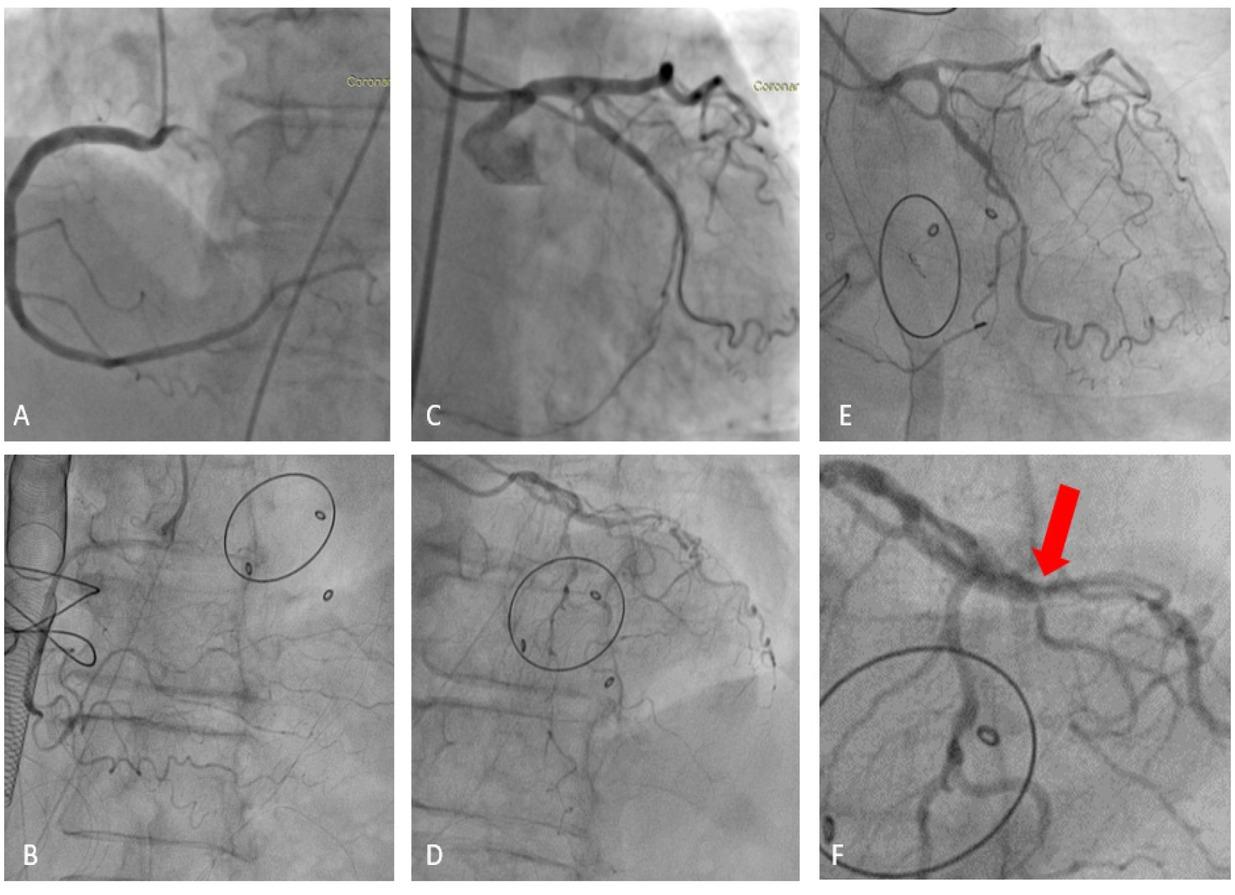

Preoperative coronary angiography revealed absence of residual stenosis with normal run-off of the circumflex coronary artery (Fig. 1 – A,C). The electrocardiogram showed atrial fibrillation. Laboratory test results revealed moderate thrombocytopenia.

The patient was emergently transferred to the catheterization lab and the angiography showed diffuse occlusive coronary artery vasospasm (Fig. 1 – B, D), ameliorated after intra-coronary administration of nitroglycerin (Fig 1 – E).

Comparative view of the coronary arteries – preoperative and postoperative aspect (A: Preoperative coronary findings – right coronary artery. B: Postoperative coronary findings – right coronary artery with severe vasospasm. C: Preoperative coronary findings – left anterior descending artery and circumflex artery with permeable DES. D: Postoperative coronary findings – left anterior descending artery and circumflex artery with severe vasospasm. E: Postoperative coronary findings – left anterior descending artery and circumflex artery after administration of Nitroglycerin). F: Stent-edge vasospasm.